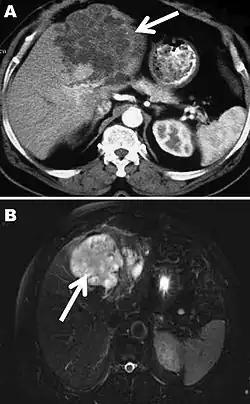

The diagnosis of polycystic echinococcosis involves isolating the protoscoleces during surgery or after the patient's death in order to identify E. vogeli. Imaging, such as ultrasound and CT scans, can also be used to identify polystytic structures, but this method is not preferred as images are similar to other types of echinococcosis and liver cancer. New studies show that PCR may identify E. vogeli in the patient's tissues.[5]

Polycystic echinococcosis (PE) is an extremely lethal helminthic disease in humans, which is caused by the larval form of E. vogeli. Type I PE consists of polycystic masses in the liver and abdominal cavity. Type II also has polcystic masses in the liver and abdominal cavity, but includes hepatic insufficiency. Type III has polcystic masses in the liver and chest cavity. In type IV polycystic masses occur only in the mesenteries. Type V has calcified cysts in the liver and lung.[4] Type II seems to have the highest mortality rate due to the complications involved with hepatic insufficiency. Due to the similarities between liver cancer and polycystic echinococcosis, PE is hard to diagnose and could be deadly when metastasized to other organs.